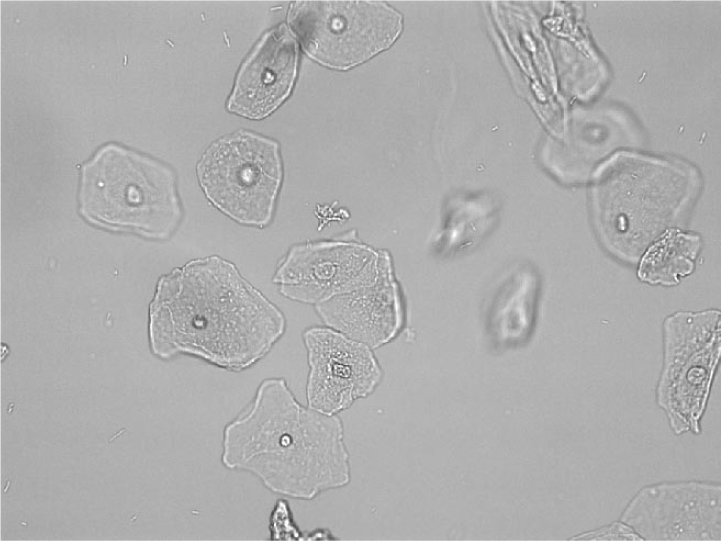

what are most of these cells

RBC

Large and flat cell with a small single nucleus

Squamous epithelial

what dese

Squamous Epithelial Cell